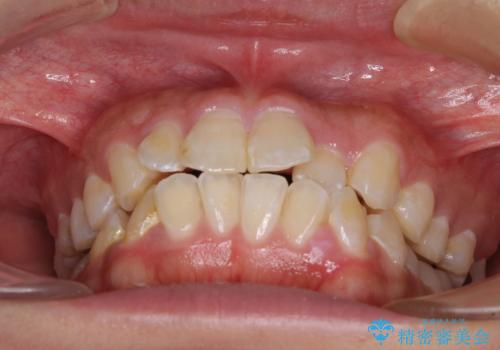

- 前歯のクロスバイトと、口元が閉じにくいとのことで来院された患者様です。

口元の突出感を改善する必要があるため、上下左右の第1小臼歯4本を抜歯し、ワイヤー装置にて矯正治療を行うこととしました。